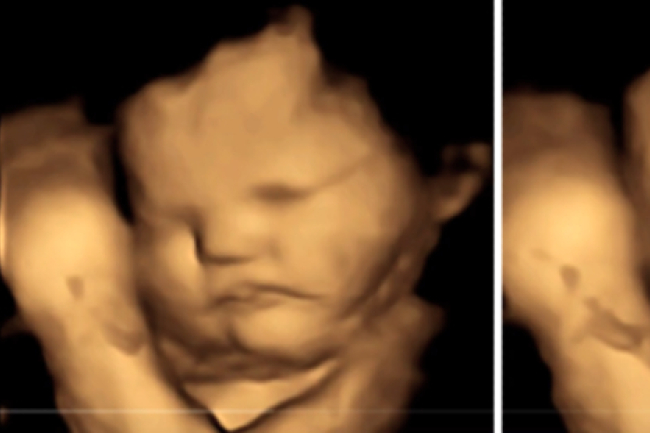

子宮嬰兒有沒有生命?3D超聲波圖片揭開秘密

子宫内的婴儿究竟有没有生命?一张3D超声波图片揭开当中秘密。